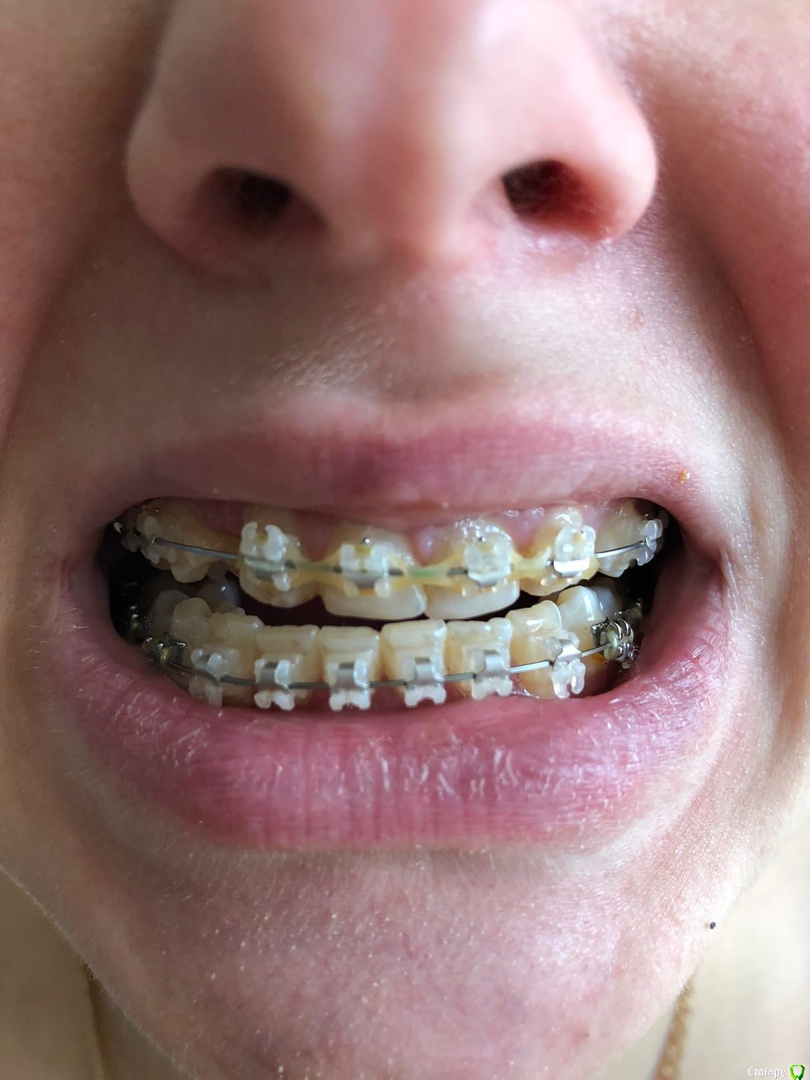

Теперь уже другой врач ставит мне опять брекеты и собирает все зубы вместе.

Главная проблема на сегодняшний день в том, что щелкает сустав  (с левой стороны), а челюсть начала уезжать в право.

Врач говорит что все пройдет когда зубы все соберутся, но я не понимаю как, ведь верх меньше на два зуба и нет вообще смыкания контакты нарушены,

да и зубы начали стирать.

Подскажите пожалуйста что делать и к кому обращаться. Сейчас мне почти 27 лет.